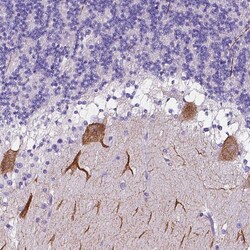

- Immunohistochemical analysis of CLSTN2 in human cerebellum using CLSTN2 Polyclonal Antibody (Product # PA5-56709) shows strong granular cytoplasmic positivity in Purkinje cells.